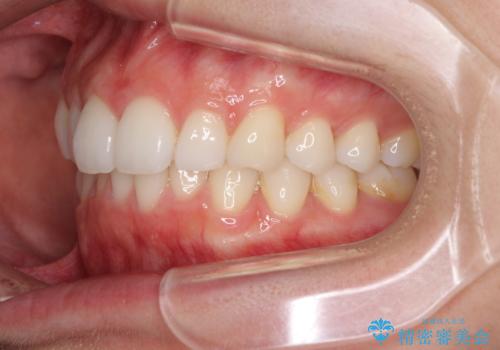

- 上下前歯の叢生を気にして来院された患者様です。

以前矯正をした後戻りということで、歯列不正はそれほど大きくなかったため、インビザライン・ライトを用いて矯正治療を行うこととしました。

前歯のデコボコが残っており、シミュレーション通りに動いていない部分がありましたが、再矯正であることやご本人の満足いくところまでデコボコが改善されたとのことで、治療を終了することとしました。